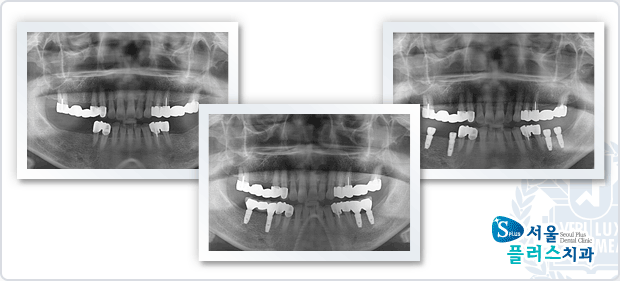

[임플란트] 임플란트 - 하악 좌우 상실부위 임플란트 식립